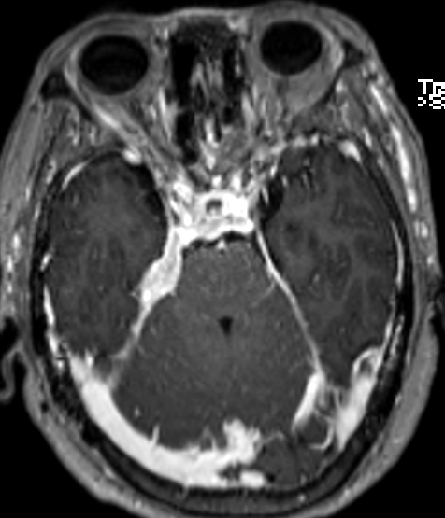

2015-4-1 MRI

2015-4-1